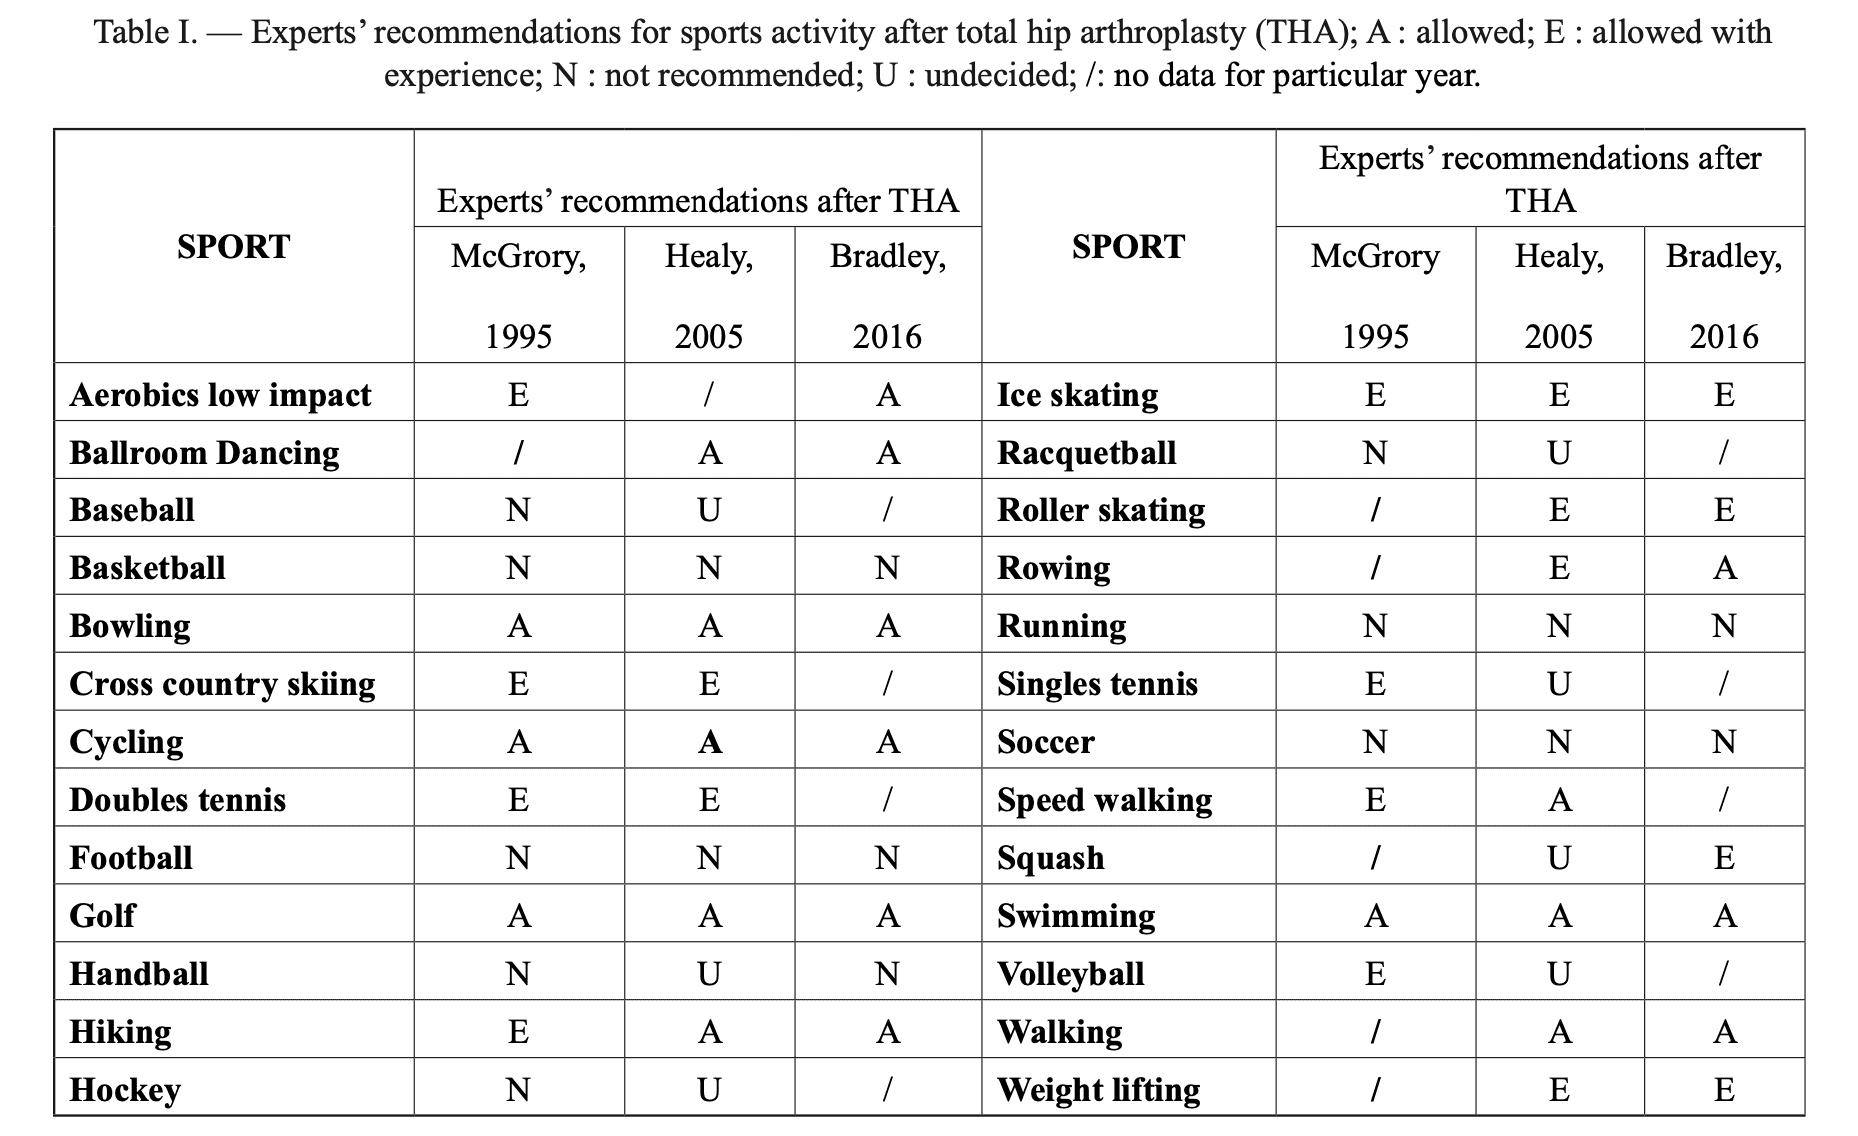

Oljaca и сътр., 2018 г., са използвали доказателствата от консенсусните документи по отношение на RTS след THA и са ги обобщили в таблицата по-долу. Можете да видите, че в много спортове доказателствата за RTS са се променили през годините.

Това изследване обобщава доказателствата, както следва: "Въпреки това, когато става въпрос за клинични резултати след TKA, изглежда, че няма разлика между пациентите с висока и ниска активност. Няма почти никаква разлика в резултатите между групите по отношение на честотата на усложненията, свързани с протезата, при спортуване с ниско до умерено въздействие. Пациентите, които не са се занимавали със спорт след THA, дори съобщават за 14,3% до 1,6% по-висока честота на смяна поради разхлабване. Когато се вземат предвид тези данни, изглежда разумно да се позволи постепенно възобновяване на спортните занимания при по-млади пациенти."

Има какво да се каже за тази обобщаваща таблица. Bender, 2022 г. измерва in vivo сили на контакт със ставите и усукващи моменти и установява, че боулингът, който се счита за дейност с ниско въздействие, например, предизвиква по-високи сили на контакт със ставите и усукващи моменти в сравнение с футбола с високо въздействие. Освен това те установяват, че телесното тегло и индексът на телесна маса оказват влияние върху тези сили по време на ежедневни дейности.

Това се потвърждава от контролирано проучване на Abe и сътр. през 2014 г., което установява, че малка част от участниците са тичали преди операцията (33 пациенти (5,4 %)), а 23 пациенти (3,8 %) са правили джогинг след операцията. Тези състезатели не съобщават за разхлабване на тазобедрената става, необичайна миграция на компонента или прекомерно износване при 5-годишно проследяване. Въпреки това в цялостния преглед на Sowers и сътр., 2023 г., асептичното разхлабване е най-често споменаваното усложнение след RTS. Следователно пациентите, които възнамеряват да възобновят дейности с голямо въздействие, като тенис, трябва да бъдат информирани за потенциалните рискове и да бъдат внимателно наблюдавани по време на обучението по RTS.